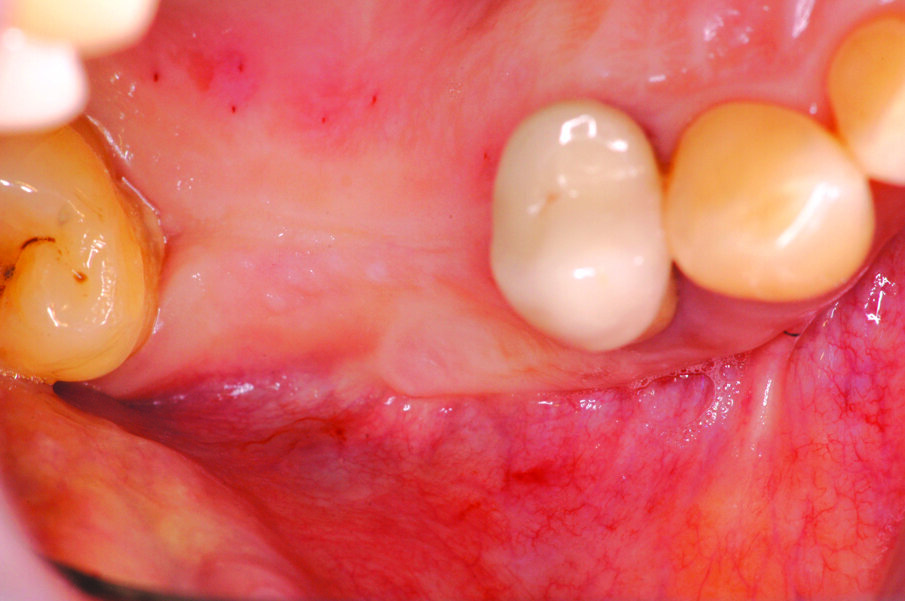

Una volta eseguito il disegno dell’antrostomia (Fig. 5), si procede al sollevamento della membrana con tecnica manuale (Figg. 6, 7) e all’iniziale inserimento di biomateriale granulare 0,5-1 mm (AlphaBio’s Graft, Alpha-Bio Tec, Israele). La corticale viene lasciata integra e aderente alla mucosa schneideriana in modo da diventare il futuro pavimento dell’antro (Fig. 8), anche per supportare il collasso della membrana durante il periodo di guarigione. A protezione della stessa è inserita una spugnetta di collagene equino (Condress, Smith&Nephew, UK). Contestualmente si procede con l’inserimento di due impianti autofilettanti SPI 3.75 x 13 mm (Alpha-Bio Tec, Israele) (Figg. 9, 10) e, al termine, viene ultimato il riempimento con biomateriale (Fig. 11). L’antrostomia viene poi coperta con una membrana riassorbibile 15 x 20 (AlphaBio’s Graft, Alpha-Bio Tec, Israele) e il lembo viene passivato e suturato con due linee di sutura 5-0: una a materassaio orizzontale e l’altra con punti staccati (Vicryl, Ethicon, USA) (Fig. 12). La paziente viene dimessa con la seguente terapia farmacologica: amoxicillina cpr 1 gr (1 cpr ogni 12h per 6 giorni), Prednisone cpr 25 mg (2 cpr per due giorni a scalare) per il controllo dell’edema post-operatorio e sciacqui con clorexidina 0.2% dal giorno successivo (1 sciacquo al giorno per 15 gg). Le suture sono rimosse a 15 giorni e la paziente è inserita in un programma di recall a cinque settimane per gestire eventuali complicanze durante la maturazione dell’innesto. Viene eseguito il secondo tempo chirurgico dopo 6 mesi e, verificata l’avvenuta osteointegrazione degli impianti, vengono rilevate le impronte e il caso è finalizzato con due corone unite in metallo ceramica (Figg. 13-15). Al termine della riabilitazione, visto il buon mantenimento igienico, la paziente viene inserita in un programma di follow-up a sei mesi (Figg. 16, 17).

Fig. 2_Visione occlusale della lacuna dentale.

Figg. 13-15_Particolari dei monconi in titanio e delle corone in metallo ceramica.